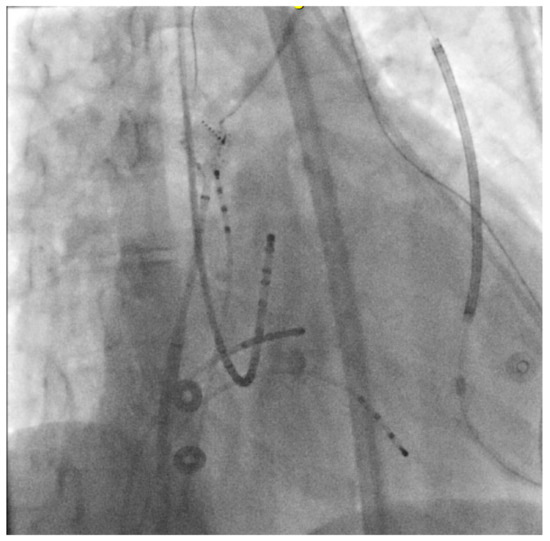

4.2.1. Cases

4.2.2. Case 1

4.2.3. Case 2